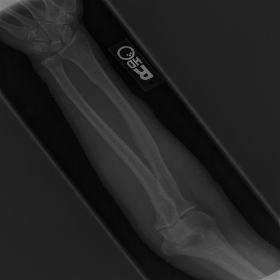

Similarly, the protection of patient records applies to MURA bone X-ray scans as well. Each hospital possesses raw images of MURA bone X-ray scans. These hospitals run the deep neural network only up to the first hidden layer using their own raw medial data, which is displayed in Figure 3 (a). The output of the first hidden layer, which is depicted in Figure 3 (b), is collected from each of the end-systems. The second image is the only information that is revealed to the server. Hence, the original medical image is protected from any and all external threats. Furthermore, as evidently demonstrated in the comparison between Figure 3 (a) and (b), even if hackers do obtain possession of the feature maps when transferring to the server, it will be very difficult to trace it back to the original image. Once again, protecting the privacy of patient information.

![]() |

| (a) | (b) |